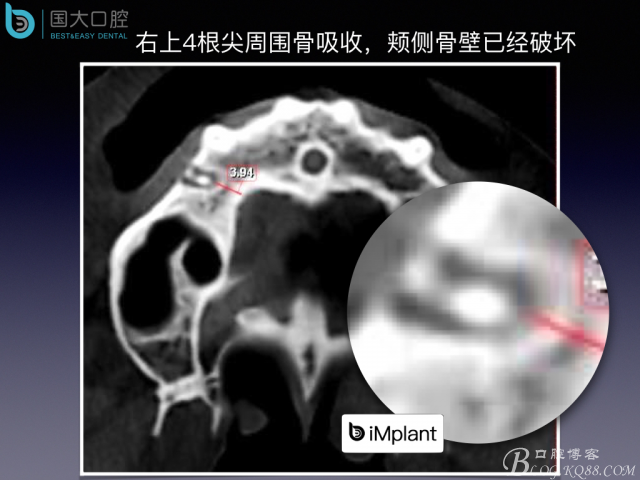

來源于國大口腔 邵現(xiàn)紅醫(yī)生發(fā)表的博文